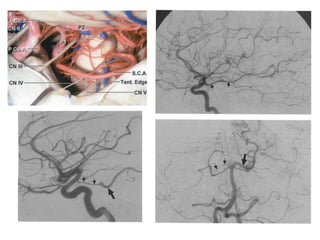

Artéria carótida cavernosa

• Está recoberta pelo gânglio trigeminal.

• Joelho posterior (mais medial) e joelho anterior (mais

lateral).

• O VI nervo é inferior e lateral a ela, no interior do seio.

Os III, IV, V1 e V2 estão na parede lateral do seio

cavernoso

• Emite três ramos importantes: tronco posterior (artéria

meningo-hipofisária), tronco ínfero-lateral e artérias

capsulares (pequenas e inconstantes).

Artéria carótida cavernosa •Está recoberta pelo gânglio trigeminal. • Joelho posterior (mais medial) e joelho anterior (mais lateral). • O VI nervo é inferior e lateral a ela, no interior do seio. Os III, IV, V1 e V2 estão na parede lateral do seio cavernoso • Emite três ramos importantes: tronco posterior (artéria meningo-hipofisária), tronco ínfero-lateral e artérias capsulares (pequenas e inconstantes).